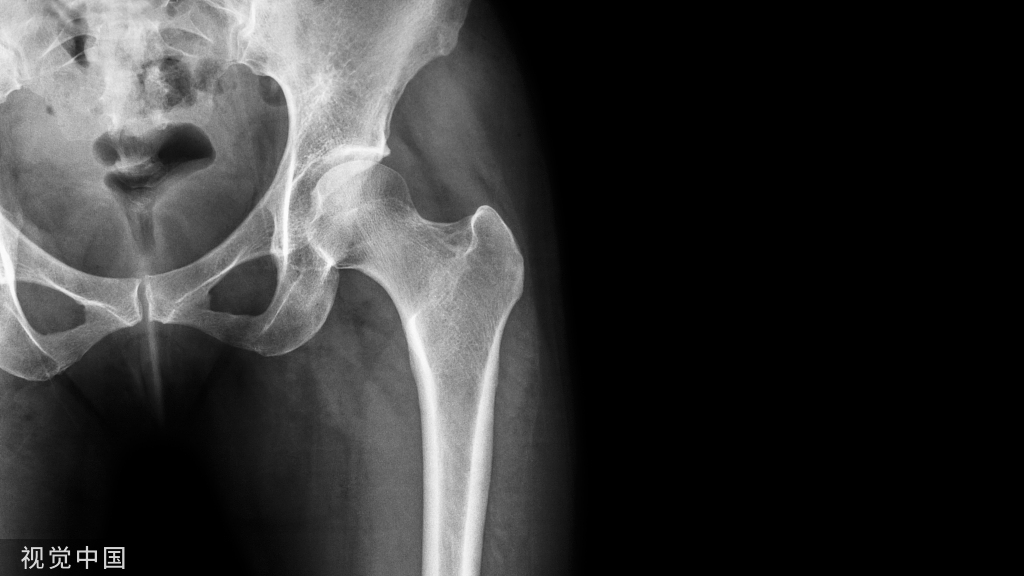

03髋关节活动范围